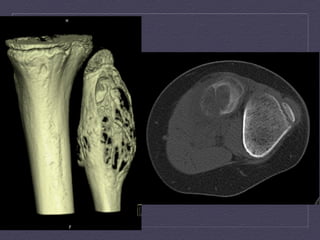

Axial  and  coronal  CT  demonstrates  septated,  ly:c  lesion  in  the   intertrochanteric  region  with  significant  thinning  of  the  posterior  cortex